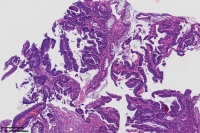

中分化腺癌?

直肠占位

腺癌(低一中 分化)

中分化腺癌

支持楼主意见。